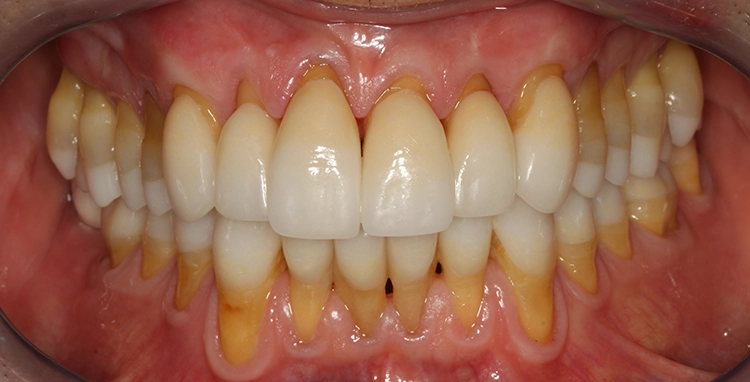

Egger/Wermuth/GrevenRote Ästhetik: Im Ober- und Unterkiefer zeigten sich generalisiert ausgedehnte Rezessionen mit bis zu 8 mm Attachmentverlust vor allem im Bereich der Eckzähne (Miller-Klasse III; Rezessionstyp [RT] 2 [69]. Das Band an keratinisierter Schleimhaut ist durchgehend vorhanden. Die Breite variiert im Eckzahnbereich von 1 mm bis zu 2 mm im Bereich der Unterkieferfrontzähne, der Prämolaren und Molaren (Abb. 1). Die fazialen Rezessionen sind mit approximalem röntgenologischem Attachmentverlust im koronalen Wurzeldrittel (Abb. 2) und Papillenverlust im Bereich zwischen den Kontaktpunkten und der approximalen Schmelz-Zement-Grenze assoziiert (Abb. 1). Der Patient verfügt über eine schmal geformte Oberlippe. Die Lachlinie verläuft mittelhoch (Abb. 3).

Parodontale Gesundheit bei Attachmentverlust, Bruxismus, Erosion. Abbildung 1 sowie 6 bis 9 zeigen den Anfangsbefund als intraoralen Fotostatus.*